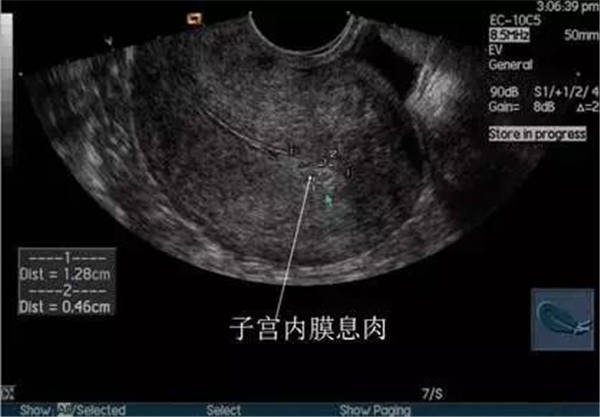

2、宫腔积血、积脓、积液

(宫腔积液)